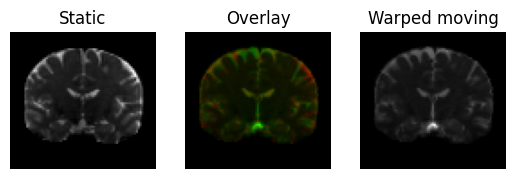

Now let’s warp the moving image and see if it gets similar to the static image

warped_moving = mapping.transform(moving)

We plot the overlapped middle slices

regtools.overlay_slices(

static,

warped_moving,

slice_index=None,

slice_type=1,

ltitle="Static",

rtitle="Warped moving",

fname="warped_moving.png",

)

<Figure size 640x480 with 3 Axes>

Moving image transformed under the (direct) transformation in green on top of the static image (in red).